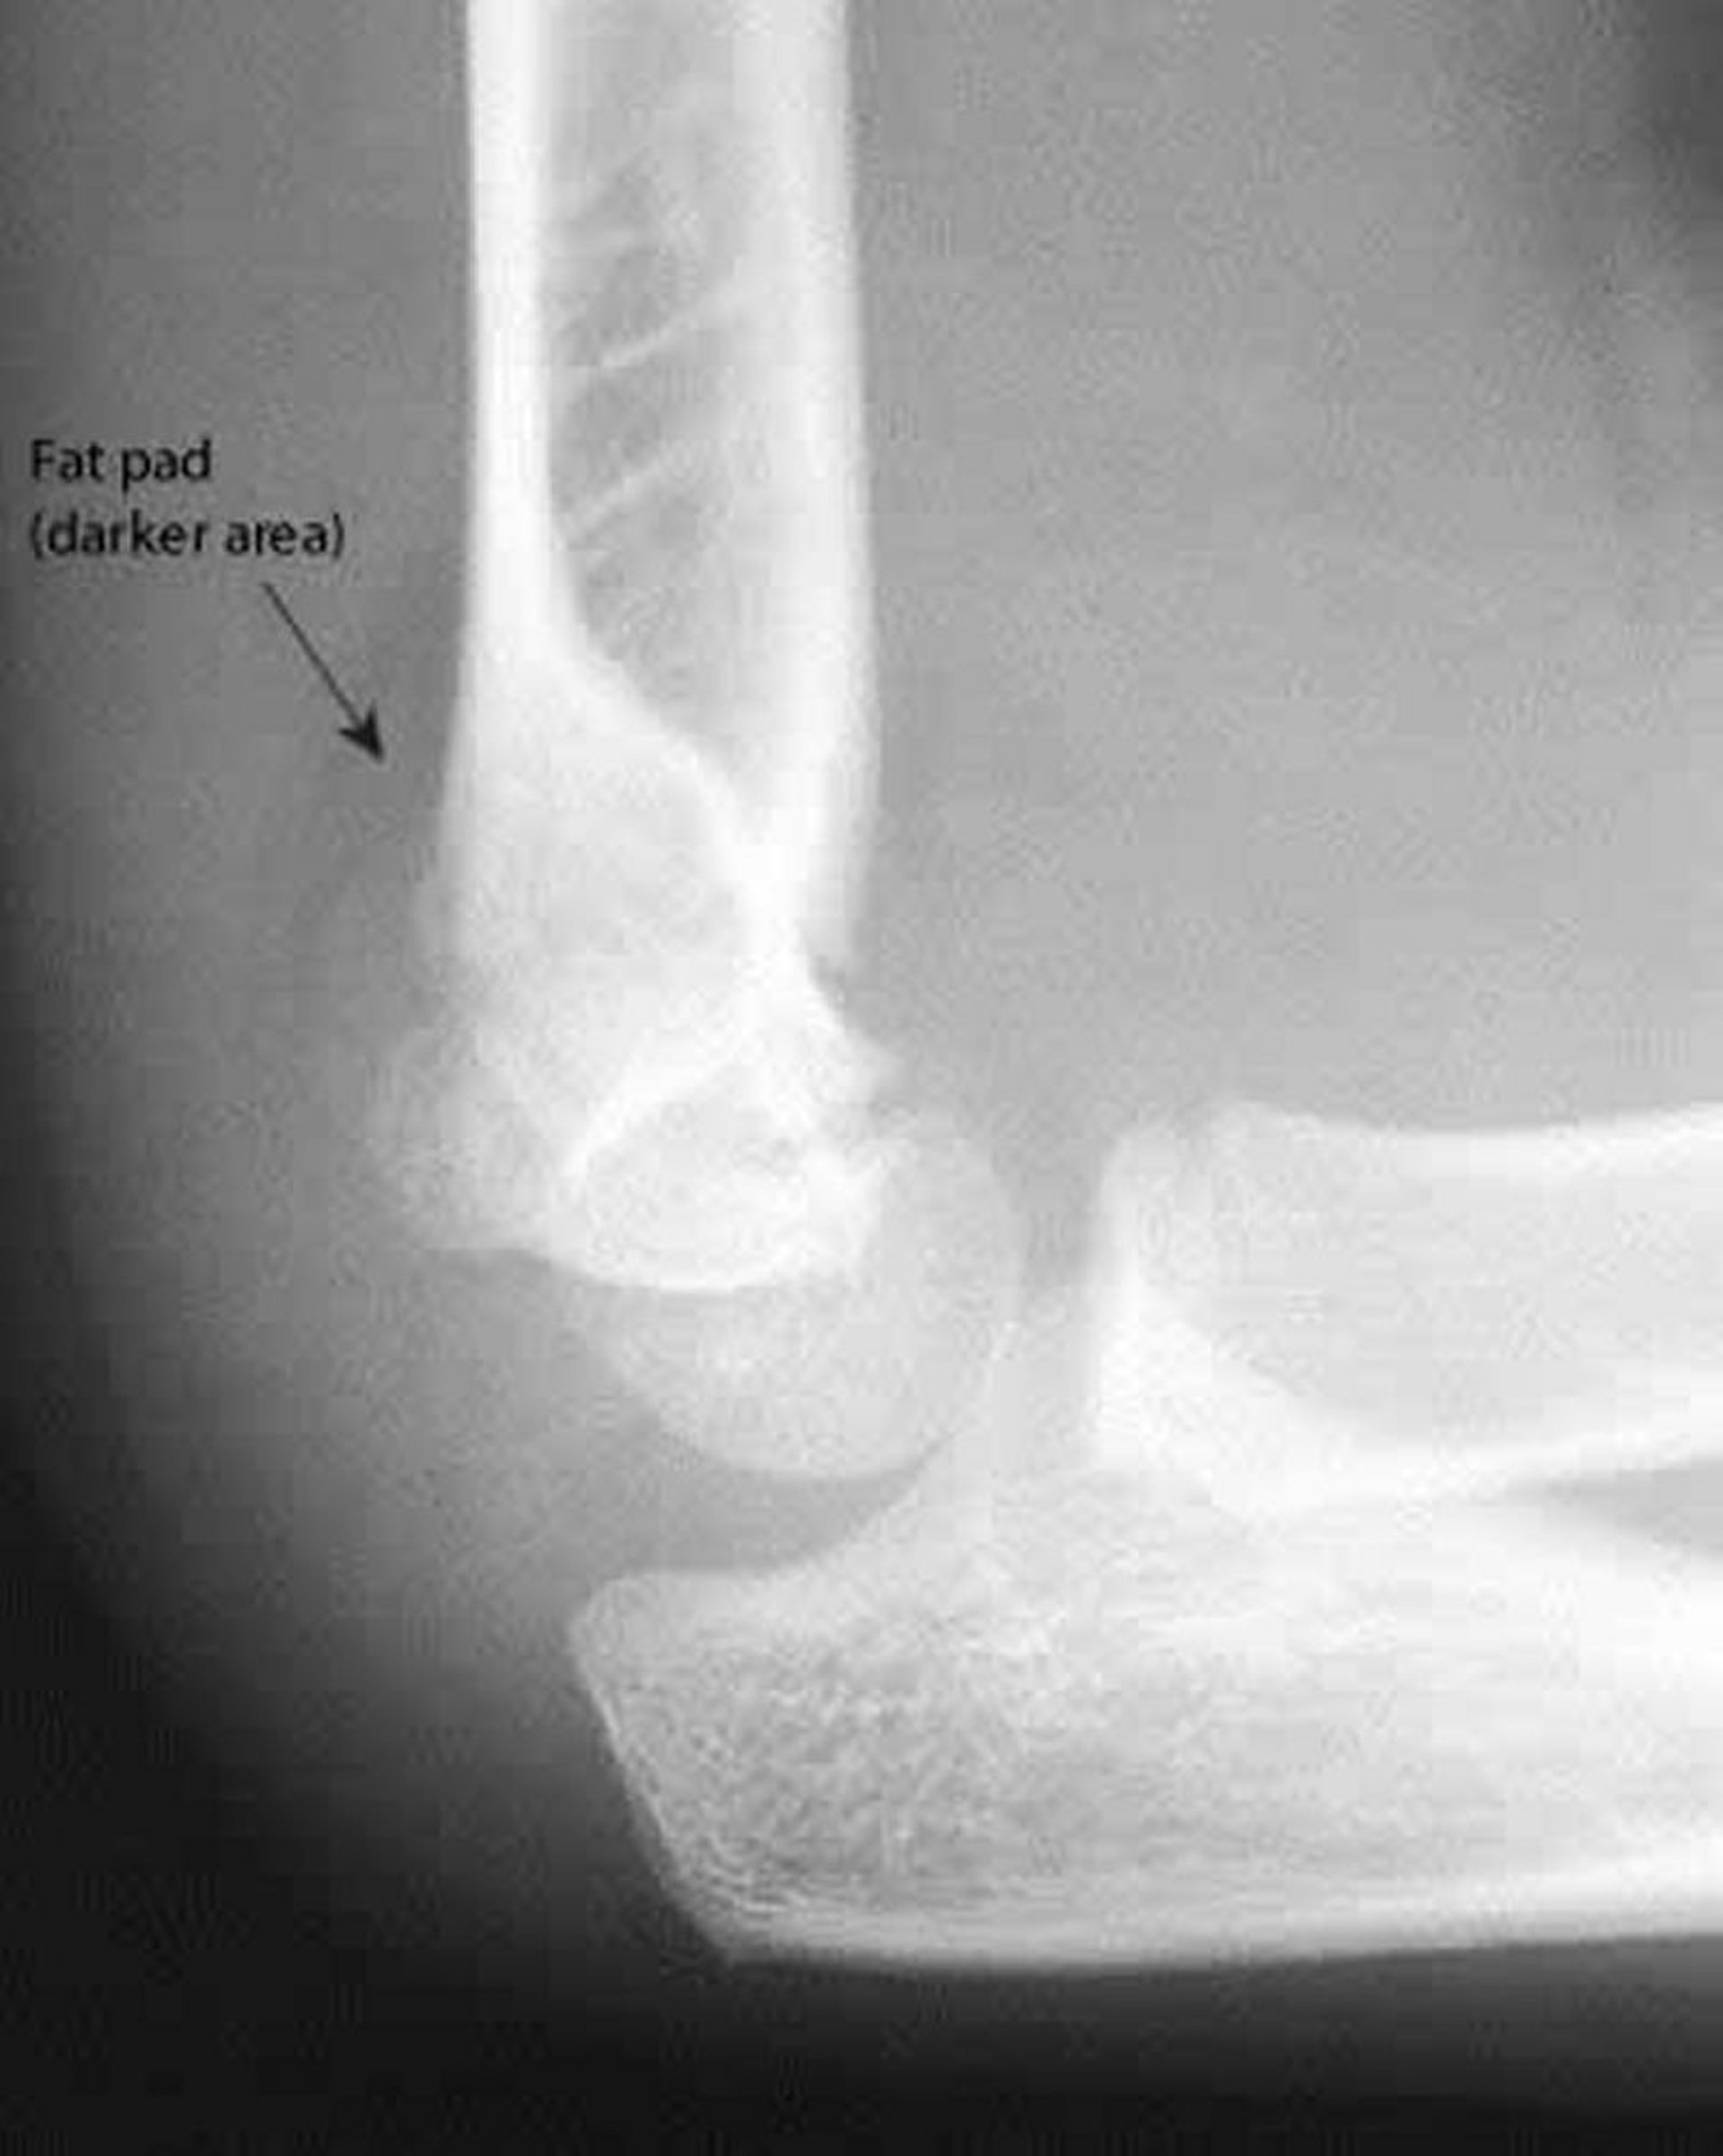

Coussinet adipeux postérieur

Un coussinet adipeux postérieur est toujours anormal. Également sur cette radiographie, la ligne humérale antérieure ne coupe pas le milieu du capitellum (condyle de l'humérus).

Image courtoisie de Danielle Campagne, MD.